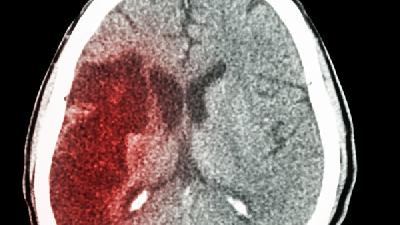

新生兒痙攣型大腦性癱瘓是媽媽遇到的最為棘手的難題,而此病的出現(xiàn)會(huì)伴隨著許許多多的癥狀,家長(zhǎng)一定要正確了解腦癱的癥狀表現(xiàn)才能夠把握治療的最佳時(shí)機(jī),從而有效的治療腦癱,使患兒早日脫離病痛,恢復(fù)健康,接下來為大家分享一下腦癱的癥狀

區(qū)分腦癱與發(fā)育遲緩需結(jié)合神經(jīng)影像學(xué)檢查、運(yùn)動(dòng)功能評(píng)估、發(fā)育量表測(cè)試及實(shí)驗(yàn)室檢查等綜合判斷。 1、神經(jīng)影像學(xué): 頭...